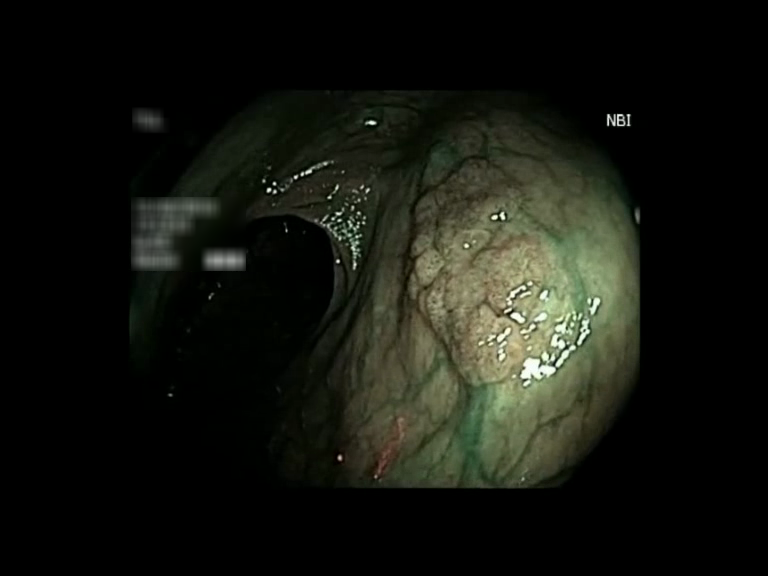

| Lesion | White Light Frame | NBI Frame | White Light Video | NBI Video | Camera Calibration |

| serrated_01 |  |

|

WL.mp4 | NBI.mp4 | cam.xml |